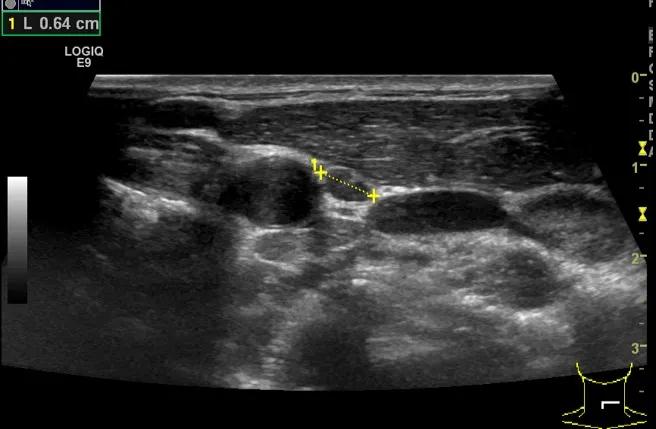

第三例是甲状腺癌患者,双侧甲状腺癌切除术后、碘治疗后一年余效果欠佳,超声显示左颈3区3枚低回声结节,穿刺示甲状腺乳头状癌转移。患者不愿意手术,希望采取局部治疗。对病灶进行液体隔离后采取热消融术,由于淋巴结较小,热消融一分钟左右完全灭活,术后增强影像显示没有脏器充填。

(病例3图例)